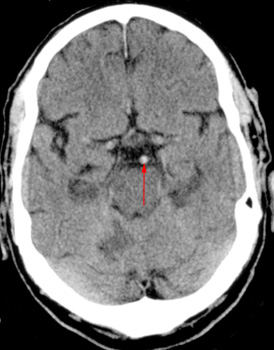

When

analyzing the CT of a potential stroke victim, one of the first findings

to look for is the presence or absence of hemorrhage. Another common finding

in stroke patients is a dense middle cerebral artery or a dense basilar

artery, which corresponds to thrombus in the affected vessel. There are

also more subtle changes of acute ischemia due to edema which include

the following:

- Obscuration of the lentiform nuclei

- Loss of insular ribbon

- Loss of gray/white distinction

- Sulcal effacement